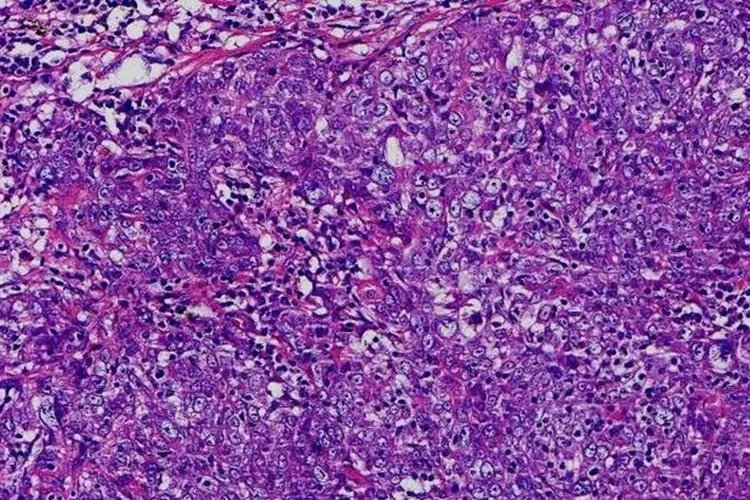

浸润与转移癌细胞具有浸润性与转移特性,正常细胞由于彼此间存在一定的黏着力,限制了细胞向附近及远处的扩散。而癌细胞表面细胞黏着与连接相关的成分发生变异或缺失,相关信号通路受阻,细胞失去与细胞间或细胞外基质间的联结,易于从原发部位脱落并且侵入周围组织,或侵入血液、淋巴组织,通过血液与淋巴液的循环,播散到身体的其他部分,造成癌的扩散与转移。